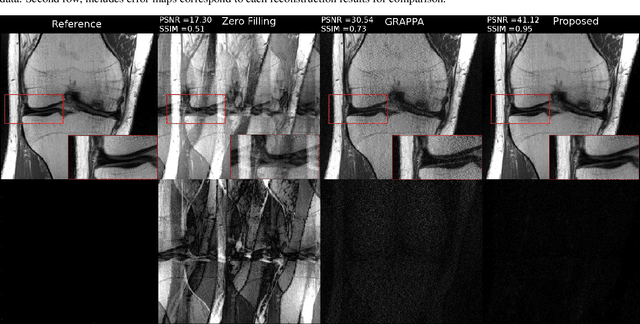

Fast data acquisition in Magnetic Resonance Imaging (MRI) is vastly in demand and scan time directly depends on the number of acquired k-space samples. Conventional MRI reconstruction methods for fast MRI acquisition mostly relied on different regularizers which represent analytical models of sparsity. However, recent data-driven methods based on deep learning has resulted in promising improvements in image reconstruction algorithms. In this paper, we propose a deep plug-and-play prior framework for parallel MRI reconstruction problems which utilize a deep neural network (DNN) as an advanced denoiser within an iterative method. This, in turn, enables rapid acquisition of MR images with improved image quality. The proposed method was compared with the reconstructions using the clinical gold standard GRAPPA method. Our results with undersampled data demonstrate that our method can deliver considerably higher quality images at high acceleration factors in comparison to clinical gold standard method for MRI reconstructions. Our proposed reconstruction enables an increase in acceleration factor, and a reduction in acquisition time while maintaining high image quality.